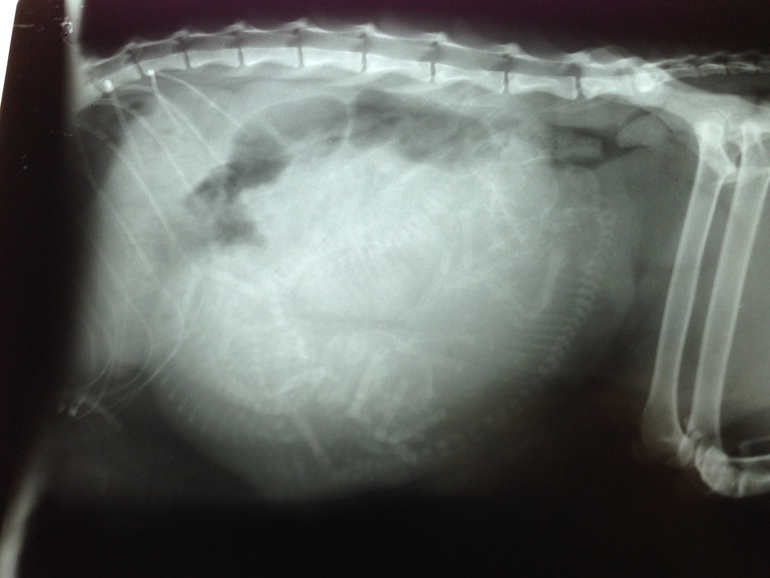

Итак,вчера сделали снимок(65 день Б),сказали 3 котенка,точно,хотя я подозревала 4-5!

Поставили катетер,влили кальций и поехали домой,жду я котят уже с 1 окт и сплю в детской кроватке -машине все эти дни с Лю караулю ее)